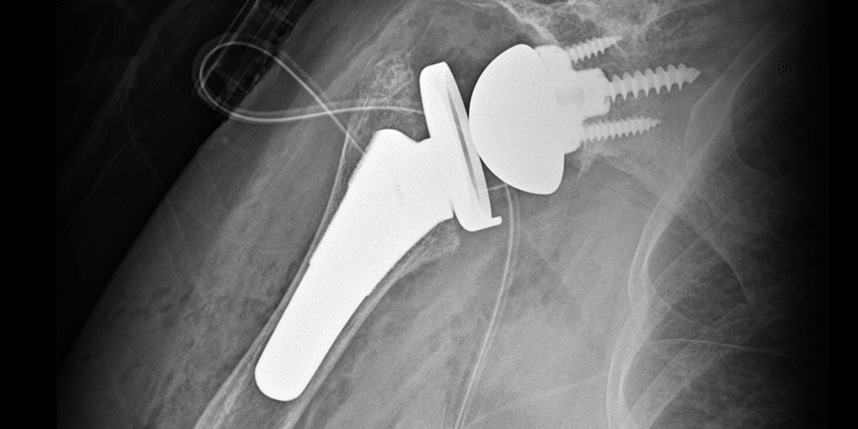

삼하게 망가져 거의 기능이 없는 관절을 제거한 후 특수하게 제작된 인공관절을 삽입하는 수술

역행성 인공관절 전치환술

역행성 인공관절 진치환술

(회전근개 심한 파열 및 관절염 진행)

* 환자에게 받은 소중한 자료입니다.